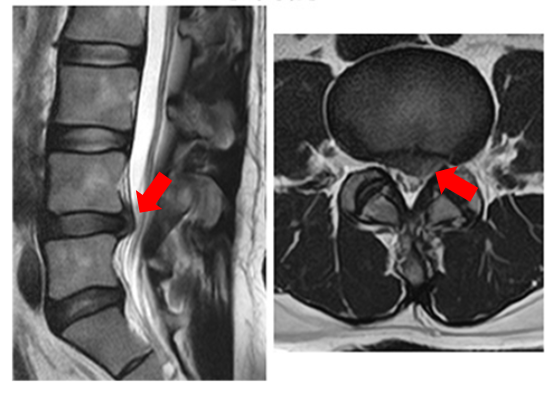

腰椎椎間板ヘルニアは、背骨の間にある椎間板(クッションのようなもの)が、脊柱管内に飛び出して神経を圧迫し、腰痛や痺れなどが出現する疾患です。坐骨神経痛の最も一般的な原因とも言われています。